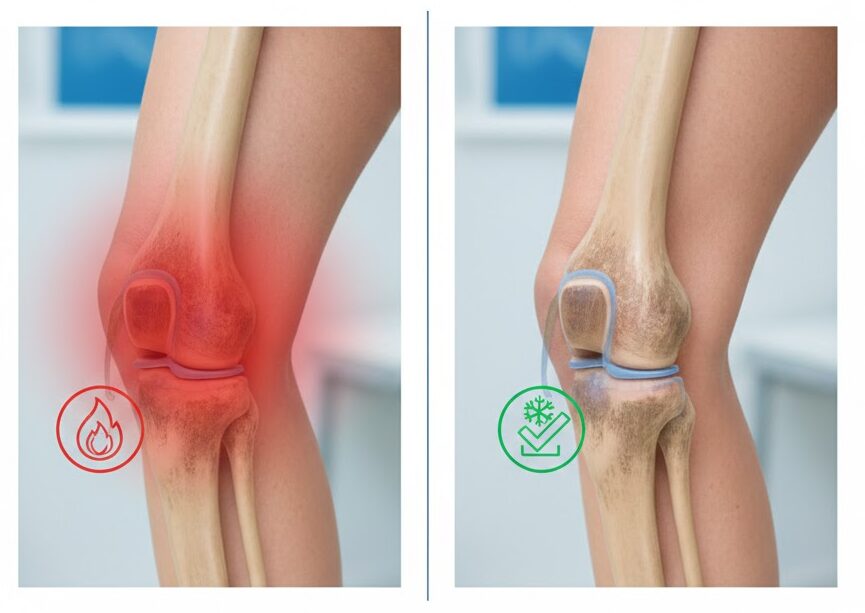

דלקות כרוניות, כאבי שרירים, התאוששות איטית מפציעות – כל אלה מאטים אותנו ומפריעים לנו לחזור לשגרה.

טיפול בקריוטרפיה הוא טכנולוגיה רפואית מתקדמת שמשתמשת בקור אינטנסיבי ומבוקר כדי להפחית דלקות, להזרים דם עשיר בחמצן לאזורים הפגועים, ולהאיץ את תהליך הריפוי הטבעי של הגוף – בלי תרופות, בלי פולשנות.

אתם מרגישים את הכאב כל בוקר כשאתם קמים. האזור תפוס, נפוח, רגיש למגע. אתם מנסים להמשיך את האימונים, לחזור לשגרה, אבל משהו מושך אתכם אחורה – הדלקת לא עוברת, השריר לא משתחרר, הכאב חוזר שוב ושוב.

ניסיתם קרח, ג'ל, משככי כאבים. זה עוזר לזמן קצר, אבל אחר כך הכל חוזר. כי הבעיה לא באמת נפתרה – הדלקת עדיין שם, זרימת הדם לאזור לא מספיק טובה, והגוף פשוט לא מצליח להחלים מספיק מהר.

שלב 3: הפחתת דלקת וחומרים דלקתיים

הטיפול מפחית את הייצור של אנזימים וחומרים דלקתיים (כמו ציטוקינים והיסטמין) שגורמים לכאב ולנזק לרקמות. התוצאה: דלקת נרגעת, כאב יורד, ותהליך הריפוי מואץ.